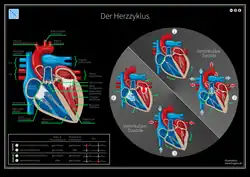

Während eines Herzzyklus füllen sich zunächst die Vorhöfe, während gleichzeitig die Kammern das Blut in die Arterien auswerfen. Wenn sich die Kammermuskulatur entspannt, öffnen sich die Segelklappen und das Blut fließt, gesaugt durch den Druckabfall in den Kammern, aus den Vorhöfen in die Kammern. Unterstützt wird dies durch ein Zusammenziehen der Vorhöfe (Vorhofsystole). Es folgt die Kammersystole. Hierbei zieht sich die Kammermuskulatur zusammen, der Druck steigt an, die Segelklappen schließen sich und das Blut kann nur durch die nun geöffneten Taschenklappen in die Arterien ausströmen. Ein Rückfluss des Blutes aus den Arterien während der Entspannungsphase (Diastole) wird durch den Schluss der Taschenklappen verhindert. Die Strömungsrichtung wird also allein durch die Klappen bestimmt.

Neben der Muskulatur, dem weitaus größten Teil der Gewebemasse des Herzens, besitzt das Herz ein sogenanntes Herzskelett. Es handelt sich hier um eine bindegewebige Struktur, die hauptsächlich aus den „Einfassungen“ der Ventile besteht. Das Herzskelett hat drei wichtige Funktionen: Es dient als Ansatz für die Muskulatur, als Ansatz für die Herzklappen (daher auch als Ventilebene bezeichnet) und zur elektrischen Trennung von Vorhof- und Kammermuskulatur, um eine gleichzeitige Kontraktion zu verhindern.

Das Herzskelett ist ausschlaggebend für die Mechanik der Herzaktion: Aufgrund des Rückstoßes bei der Blutaustreibung ist die Herzspitze im Laufe des gesamten Herzzyklus relativ fixiert und bewegt sich kaum. Somit wird folglich bei einer Kontraktion der Kammermuskulatur (Systole) die Ventilebene nach unten in Richtung der Herzspitze gezogen. In der Erschlaffungsphase der Kammermuskulatur (Diastole) bewegt sich die Ventilebene wieder in Richtung Herzbasis.

Bei der Senkung der Ventilebene wird somit zum einen das Blut aus der Kammer in den Kreislauf ausgeworfen und zum anderen vergrößert sich auch der zugehörige Vorhof. Es kommt zu einem Unterdruck, wodurch Blut aus den großen Venen in die Vorhöfe strömt. Bei der Erschlaffung der Kammermuskulatur hebt sich nun die Ventilebene, wodurch die Kammern passiv über die Blutsäulen der Vorhöfe ausgedehnt werden und sich dadurch zu etwa 70–80 % füllen. Die anschließende Kontraktion der Vorhöfe pumpt nun das restliche Blut in die Kammern und leitet somit einen neuen Herzzyklus ein. Die Vorhofkontraktion ist daher nicht zwingend für das Funktionieren des Herzens nötig, was sich auch daran zeigt, dass (im Gegensatz zum Kammerflimmern) Patienten mit Vorhofflimmern durchaus lebensfähig sind.